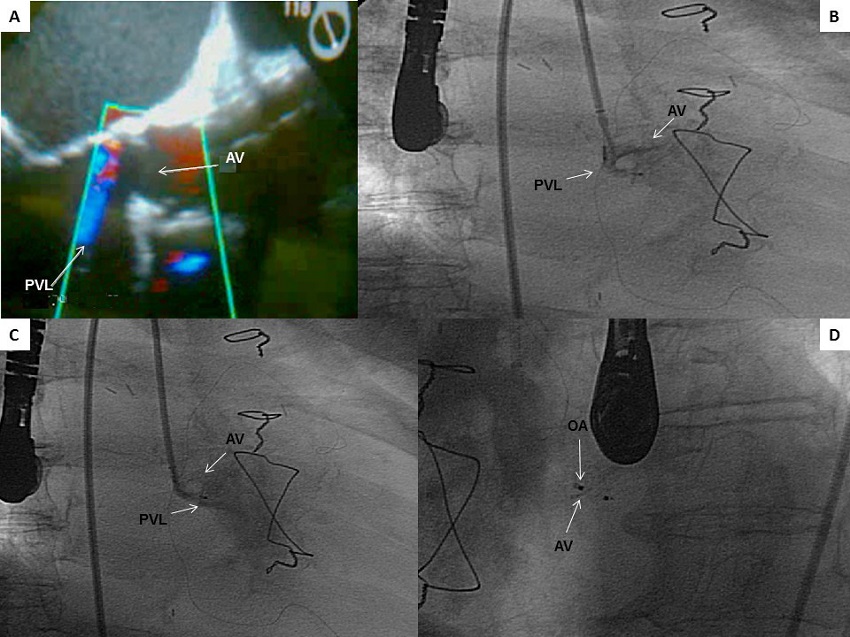

A multiplanar transthoracic and transesophageal echocardiography was performed, which showed severely damaged ventricular function and mechanical prosthetic valve in a bileaflet normal function aortic position with a PVL, leading to severe regurgitant jet (8.5 mm wide and going into the middle third of the left ventricle). The regurgitant area was 43 mm2, with no images compatible with vegetations (Figure 1A).

AV=aortic valve; OA=occlusive Amplatzer; PVL=paravalvular leak

The PVL was closed retrogradely with a right femoral artery puncture, using an 8 French introducer. First, a multipurpose catheter angiography was conducted to see the PVL (Figures 1B and C). A wire-guided multipurpose catheter was placed towards the aortic valve plane. A Terumo hydrophilic guidewire was inserted in the catheter in order to go through the PVL, and then exchange was performed via a high-support guidewire (Amplatz). Afterwards, the Amplatzer Vascular Plug III (St. Jude Medical, Plymouth, MN, USA) release system was placed, and once on the dehiscence, the transesophageal echocardiography showed the end of the leak regurgitation jet. Then, the occlusion device was released (Figure 1D), after lack of interference with the mechanical prosthesis was ensured.